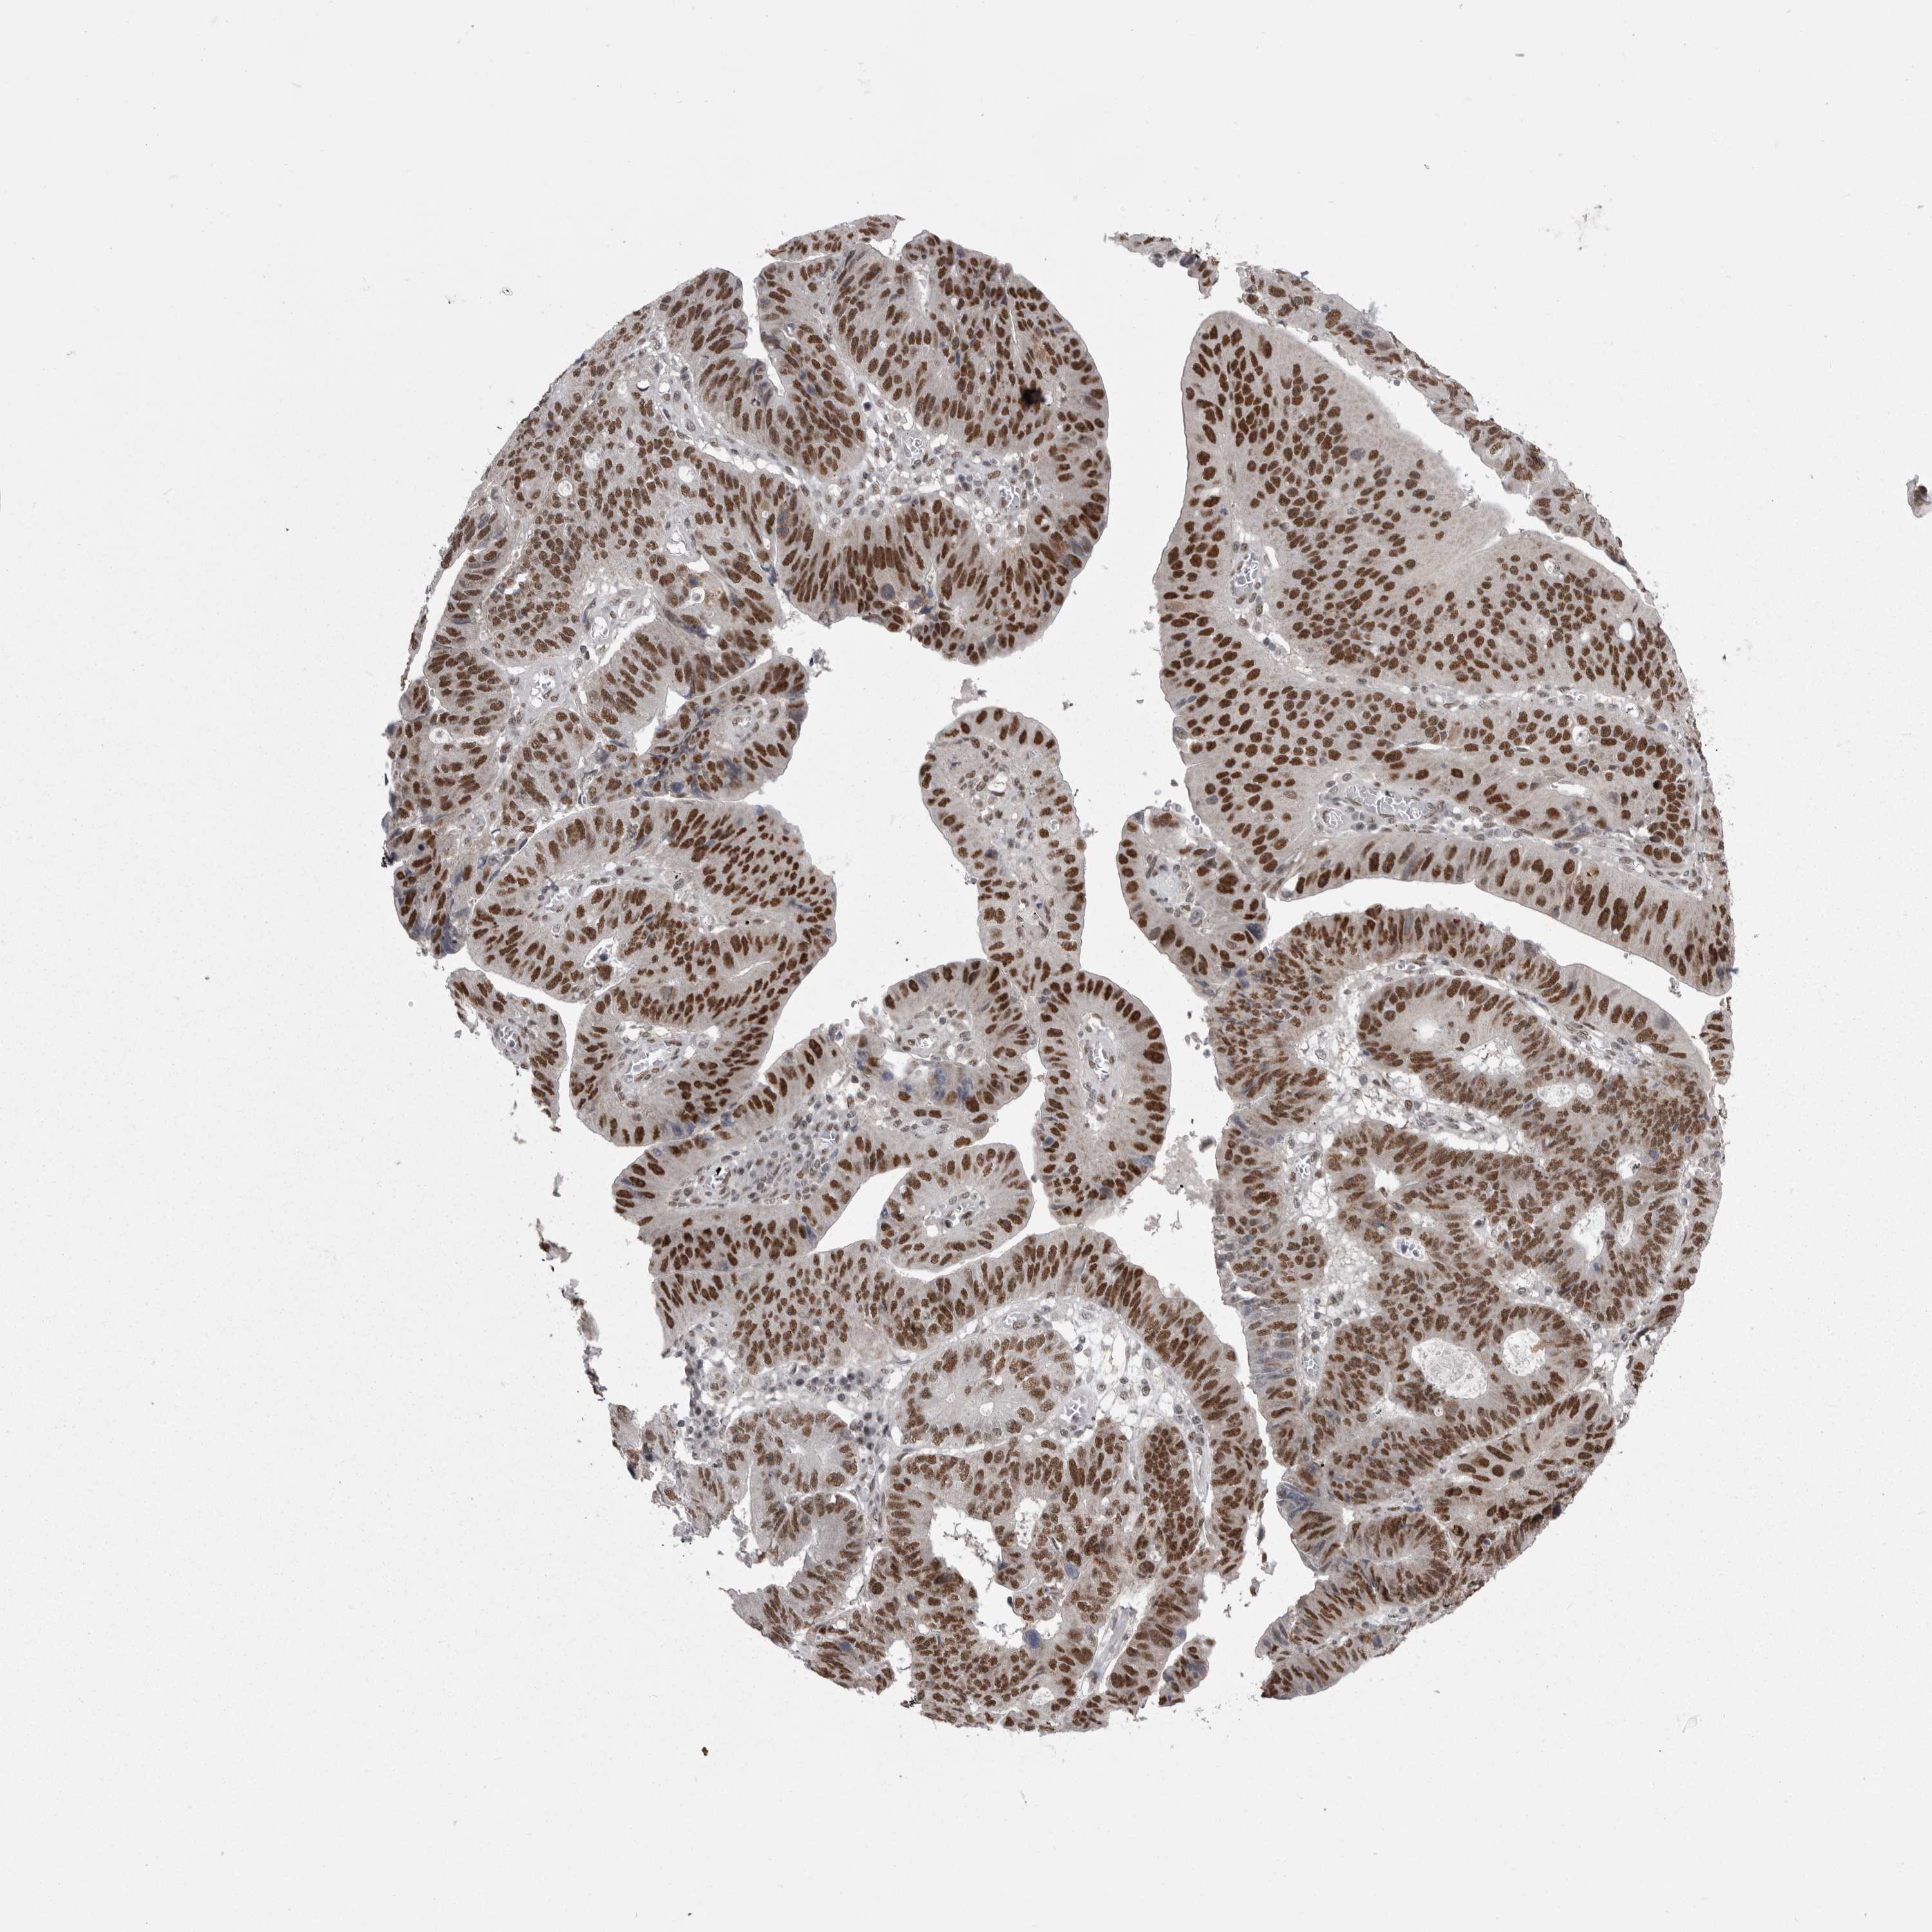

STOMACH CANCER - Protein expressioni

A mouse-over function shows sample information and annotation data. Click on an image to view it in a full screen mode. Samples can be filtered based on level of antibody staining by selecting one or several of the following categories: high, medium, low and not detected. The assay and annotation is described here.

Note that samples used for immunohistochemistry by the Human Protein Atlas do not correspond to samples in the TCGA dataset.

Antibody stainingi

Antibody staining in the annotated cell types in the current human tissue is reported as not detected, low, medium, or high, based on conventional immunohistochemistry profiling in selected tissues. This score is based on the combination of the staining intensity and fraction of stained cells.

Each image is clickable and will lead to virtual microscopy that enables deeper exploration of all samples and also displays staining intensity scores, fraction scores and subcellular localization as well as patient and tissue information for each sample.

Antibody HPA051587

Antibody CAB026384

Staining

High

Medium

Low

Not detected

Intensity

Strong

Moderate

Weak

Negative

Quantity

>75%

75%-25%

<25%

None

Location

Nuclear

Cytoplasmic/membranous

Cytoplasmic/membranous,nuclear

Adenocarcinoma, NOS